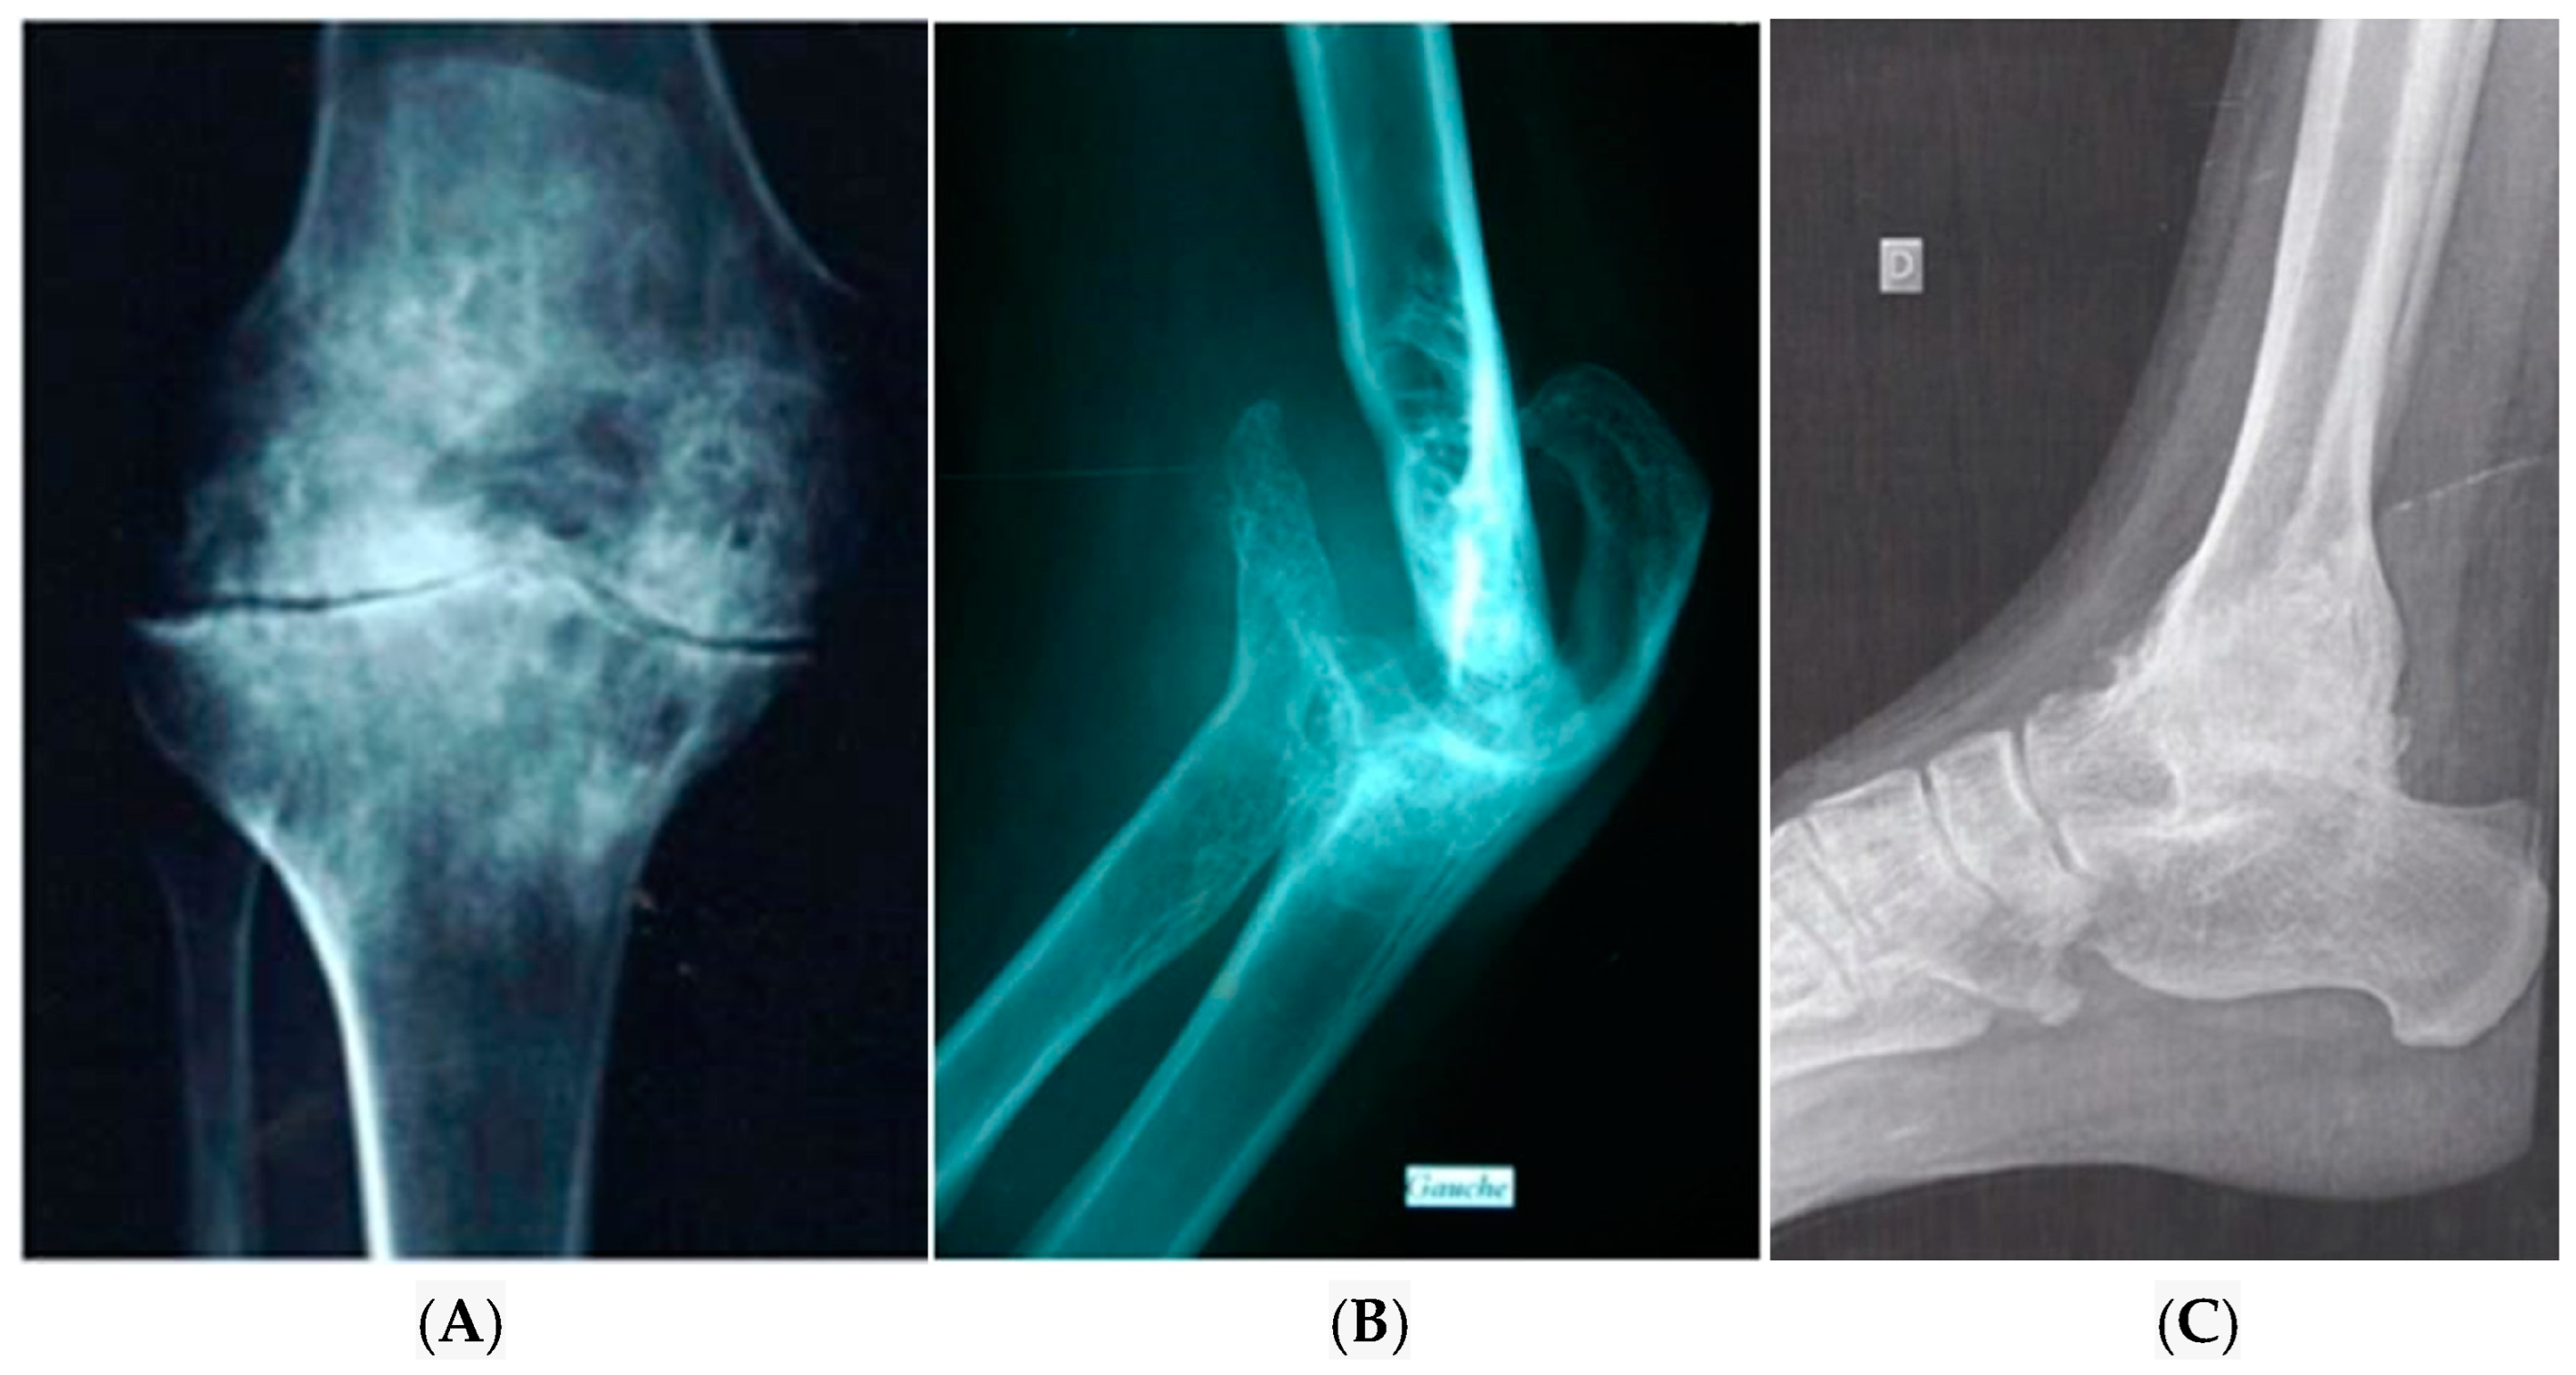

4. Diagnosis of Haemophilic Arthropathy